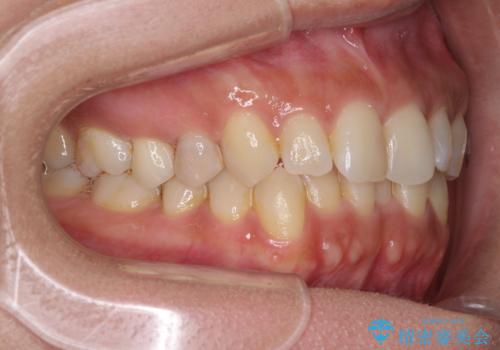

沖縄から飛行機で通院 インビザラインによる矯正治療

- 30代女性

- インビザライン

- 3年8ヶ月

- 定期的に東京に来るので、沖縄から矯正治療で通院したいとのことで来院された患者様です。

歯列不正は軽度であったので、応急処置の少ないインビザラインにて矯正治療を行うこととしました。